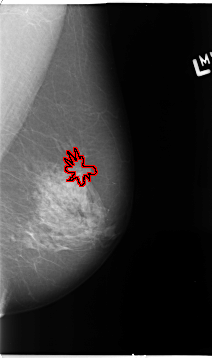

B_3093_1.RIGHT_MLO

LEFT_MLO LINES 4648 PIXELS_PER_LINE 2744 BITS_PER_PIXEL 12 RESOLUTION 50 OVERLAY

FILE: B_3093_1.LEFT_MLO.OVERLAY

TOTAL_ABNORMALITIES 1

ABNORMALITY 1

LESION_TYPE MASS SHAPE ARCHITECTURAL_DISTORTION MARGINS ILL_DEFINED-SPICULATED

ASSESSMENT 4

SUBTLETY 3

PATHOLOGY BENIGN

TOTAL_OUTLINES 1

BOUNDARY